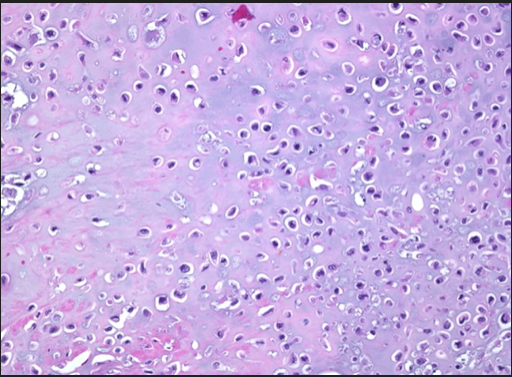

40 M with a mass in the great toe. Histology from biopsy below.

What is the most liley diagnosis?

synovial sarcoma

hsitology shows biphasic areas of spindle cell stroma and epithelial cells.

Describe the histolgy slide.